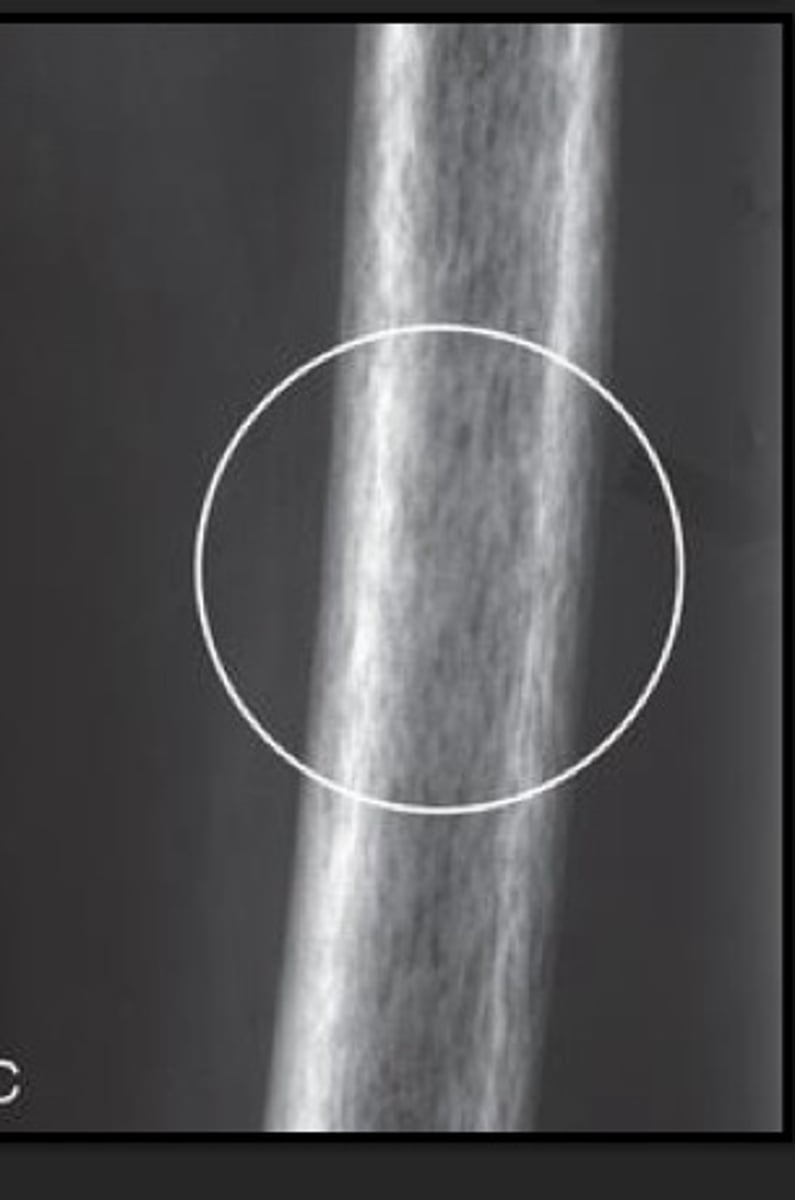

Paget's imaging